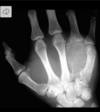

Fratura de Bennett

Fratura da base do primeiro metacarpo;

Intra-articular;

Dois fragmentos.